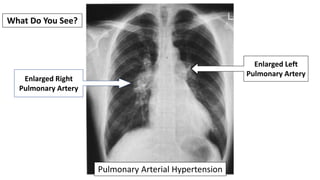

What Do You See?

Pulmonary Arterial Hypertension

Enlarged Right

Pulmonary Artery

Enlarged Left